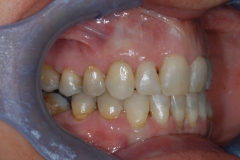

This young patient was self-conscious about the appearance of her short teeth and gummy smile. Through crown lengthening and tooth whitening procedures, we were able to create a beautiful, more mature smile.